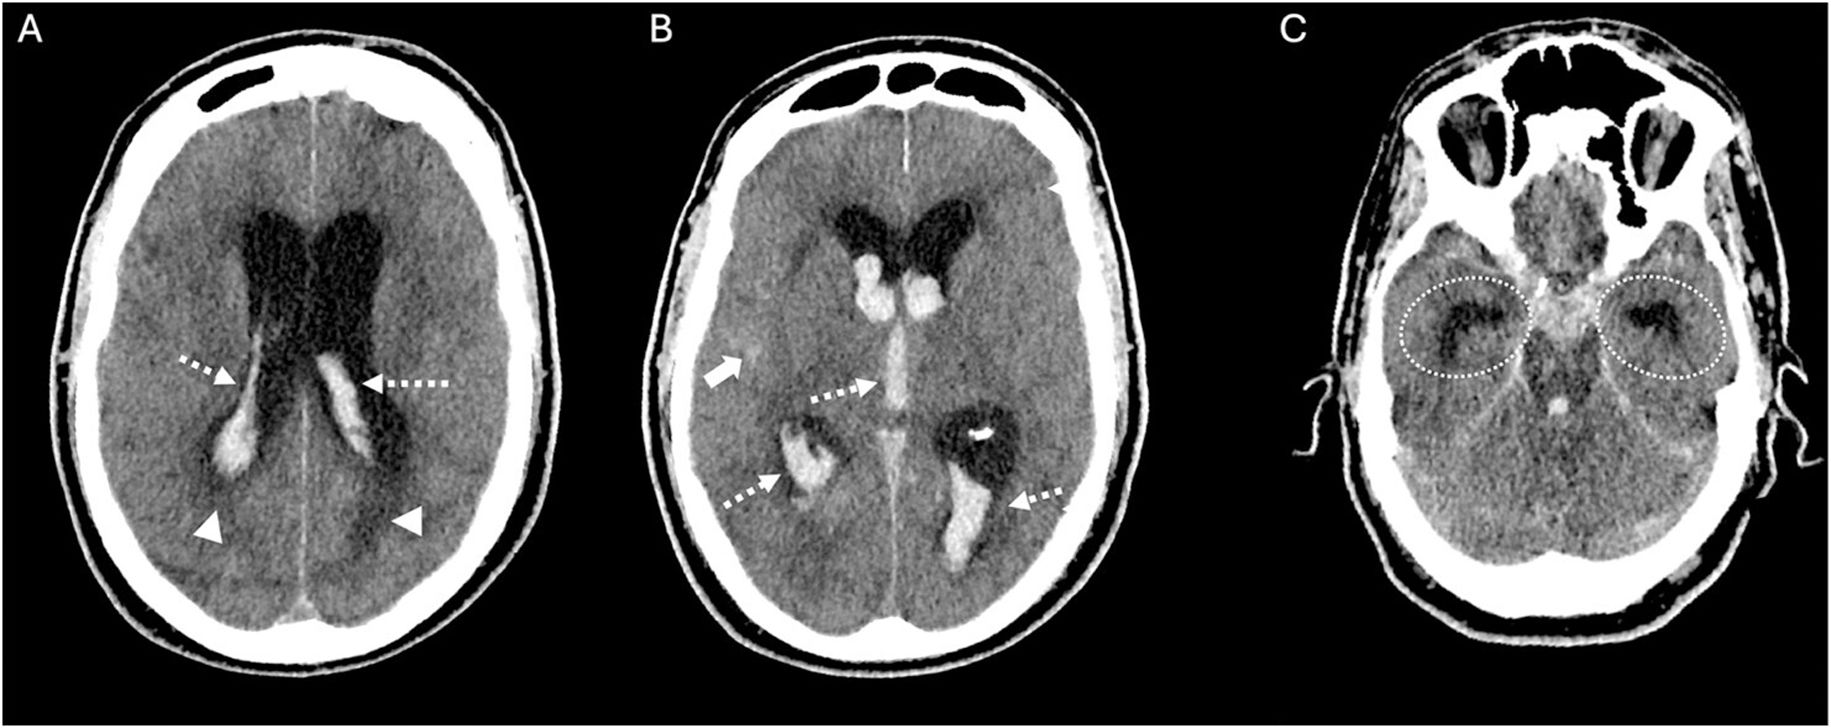

La hemorragia subaracnoidea espontánea (HSA) es una urgencia neurológica que afecta predominantemente a adultos jóvenes, con una elevada tasa de mortalidad y secuelas neurológicas graves en los supervivientes. Su manifestación clínica más característica es la cefalea súbita en trueno, considerada la peor cefalea de la vida, frecuentemente acompañada de alteraciones del nivel de conciencia y rigidez de nuca. La tomografía computarizada craneal sin contraste (TCCSC) constituye la herramienta diagnóstica inicial de elección, con alta sensibilidad. El reconocimiento de patrones de distribución del sangrado en la TCCSC permite orientar el diagnóstico etiológico y valorar la presencia de complicaciones como hidrocefalia, hemorragia intraventricular o edema cerebral. Esta primera parte del artículo proporciona una guía práctica y detallada basada en la imagen para el radiólogo en la fase hiperaguda de la HSA espontánea, diferenciando entre patrones aneurismáticos, perimesencefálicos y corticales, y discutiendo sus implicaciones clínicas, diagnósticas y terapéuticas.

Spontaneous subarachnoid haemorrhage (SAH) is a neurological emergency that predominantly affects young adults, with a high mortality rate and severe neurological sequelae in survivors. Its most characteristic clinical manifestation is a sudden thunderclap headache, often described as the worst headache of one's life, and frequently accompanied by altered levels of consciousness and neck stiffness. Non-contrast cranial computed tomography (NCCT) is the initial diagnostic tool of choice due to its high sensitivity. Recognising the distribution patterns of haemorrhage on NCCT helps guide the aetiological diagnosis and assess the presence of complications such as hydrocephalus, intraventricular haemorrhage or cerebral oedema. This article offers a practical and detailed imaging-based guide for radiologists in the hyperacute phase of spontaneous SAH, distinguishing between aneurysmal, perimesencephalic and cortical patterns, and discusses their clinical, diagnostic and therapeutic implications.